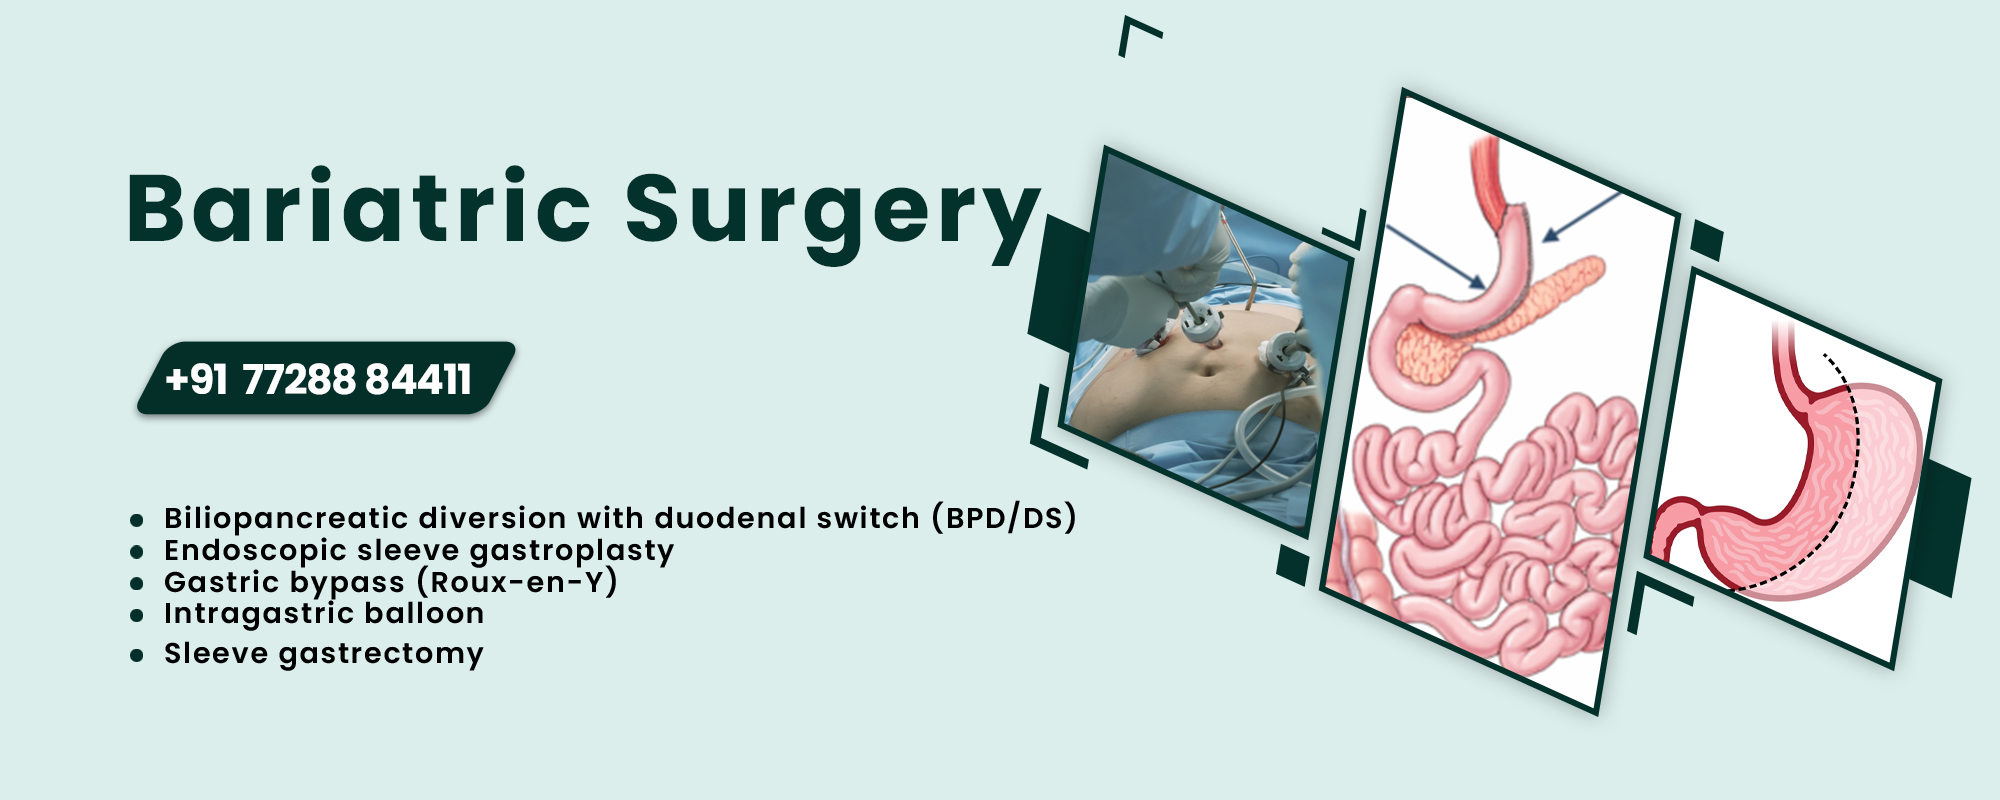

Bariatric Surgery

Gastric bypass and other weight-loss surgeries make changes to your digestive system to help you lose weight by limiting how much you can eat or..